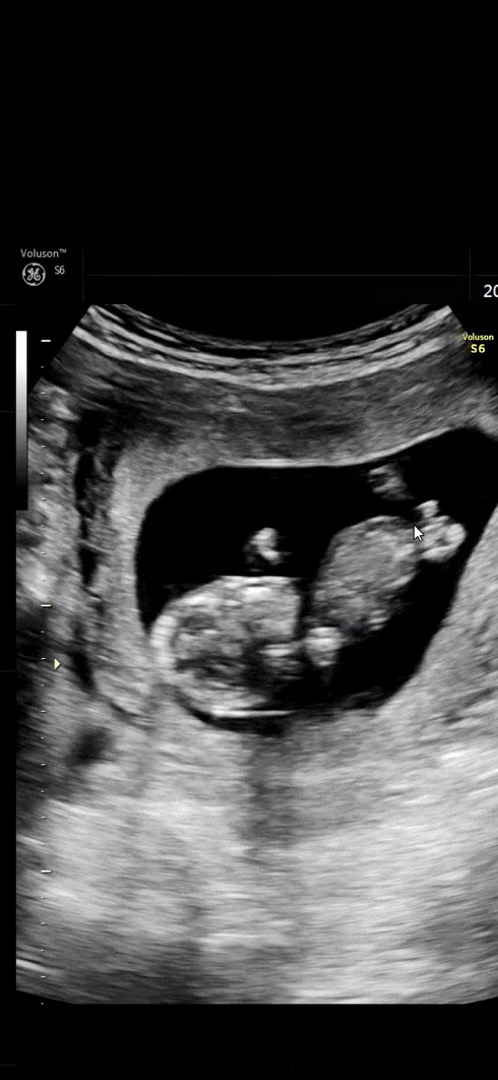

12주 다리사이 ㅎㅎ

이정도면 아들확정이겠죠